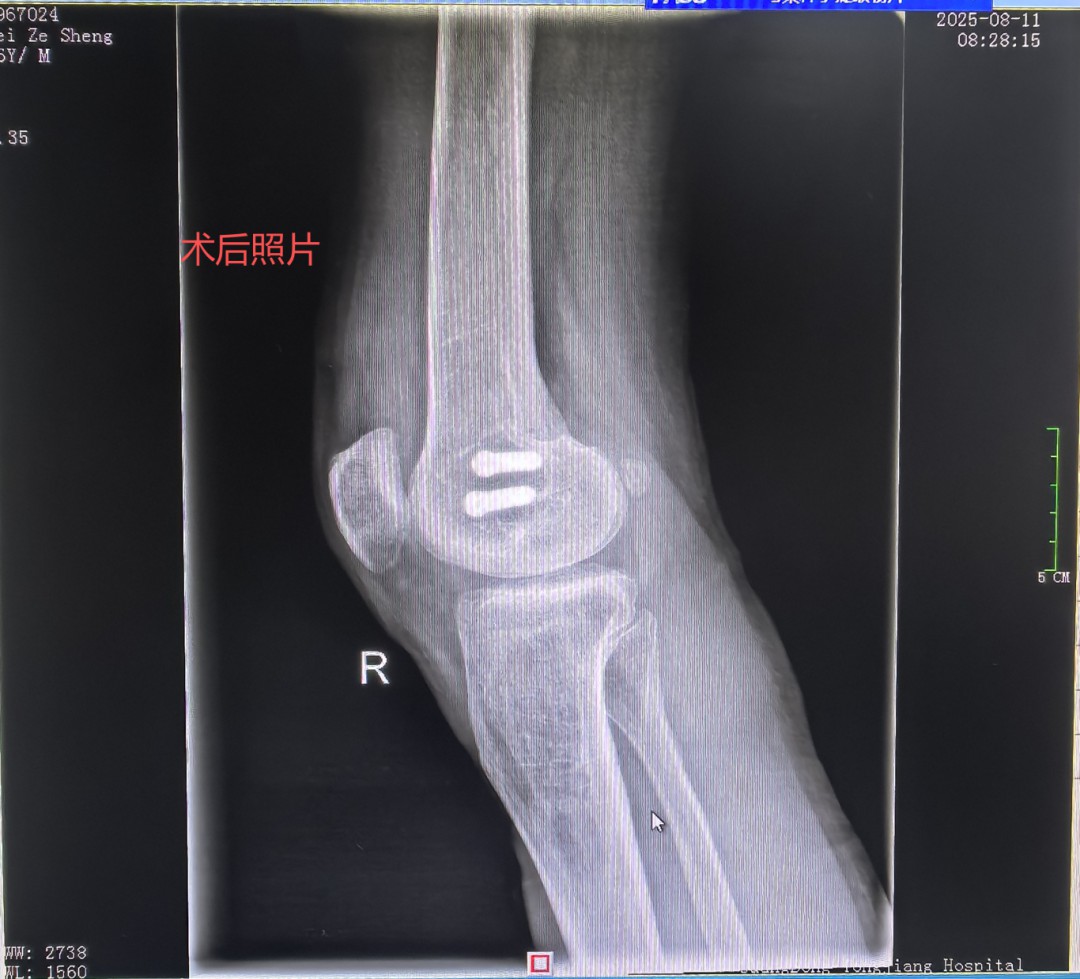

秋意初显,阳光和煦。9月20日骨二科医生办公室迎来一位熟悉的“家人”这位刚出院一个月的梅先生。他扶拐步履稳健,笑容满面,与入院时因车祸受伤平车推入院时判若两人。他此行的目的,一是回来复查,二是要亲手将一封情真意切的感谢信交到我们医务人员手中,以此表达对骨二科全体医护人员最诚挚的谢意。 时间回溯到2025年08月06日, 梅先生上班刚到单位门口车祸不慎致“右股骨髁间骨折、右膝半月板损伤”同事即送急诊后收治入我科,这次意外损伤不仅给梅先生不管是生活上还是愈合恢复都是一种困扰,伤筋动骨100天对一个家庭生活的支柱躺下来带来的困扰与焦虑也是不想而知,这175高的中年男子被这意外变得六神无主快崩溃了。 得知梅先生的意外和焦虑,骨二科罗永立主任带领团队迅速行动。马上制定精准的手术方案,于8月9日为梅先生行:右股骨髁间骨折切开复位内固定术 三分医治七分护理,徐凌峰护长带领护理团队秉承“以患者为中心”针对梅先生制定优质服务理念,从术后无痛管理、到早期快速康复功能锻炼指导,每一个环节都凝聚着我们的专业水平与人文关怀。在医、护、患三方的共同努力下,梅先生恢复神速,根据梅先生的情况术后第一天可以摇高床头坐起来,第二天可以扶床下地站,第三天扶拐下地活动。术后复查照片结果骨折对位良好,住院仅用了13天。梅先生就可以出院回家休养,这么快速可以回家?可以扶拐下地?再不是伤筋动骨100天的长期卧床等康复。家人同事与邻居看见梅先生从受伤到回家到可以下地活动,简单的生活能自理。真的让梅先生与家人象梦境一样。难以想象,便事件告诉他们这就是我们同江医院的精湛医术及优质护理。 当梅先生与古医生约好一个月要回院复查时,就带上出院后就写好的感谢信一起送到古医生手里,看见他扶拐稳健的步伐和灿烂的笑容。一封感纸短情长,字里行间充满感激的簿张却是对骨二科团队医术医德的赞誉和对护理工作的深切感激。这封信,不仅是对我们过往工作的肯定,更是鞭策我们不断前行的动力。 梅先生短短康复之旅,就是骨二科团队践行“敬佑生命、救死扶伤、甘于奉献、大爱无疆”职业精神的一个缩影。精湛的医术是根,优质的护理是叶,而患者的信任与康复,则是我们共同培育出的最甜美的果实。未来将继续用专业、爱心和担当,为每一位患者的健康保驾护航,书写更多温暖生命的奇迹! 图:患者感谢信